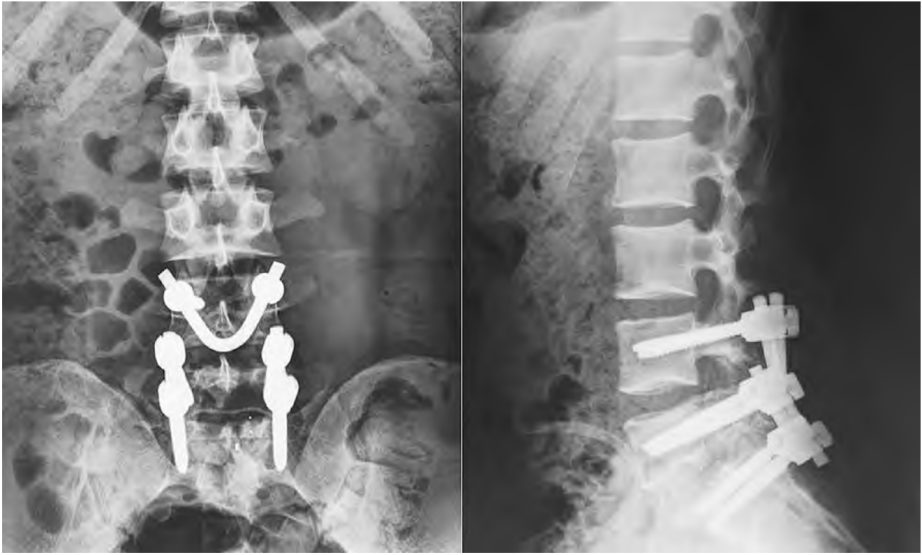

該(gai)技術于病變椎體雙側(ce)(ce)置入萬向(xiang)(xiang)椎弓(gong)根(gen)(gen)釘(ding),清(qing)理峽部(bu)斷端并(bing)植骨,將(jiang)預(yu)彎的(de)V形棒穿過棘突間隙(xi)后,將(jiang)棒兩端分別穿過兩側(ce)(ce)萬向(xiang)(xiang)椎弓(gong)根(gen)(gen)釘(ding)尾部(bu),將(jiang)棘突向(xiang)(xiang)頭(tou)側(ce)(ce)適當推壓提拉,加壓峽部(bu)斷端后鎖緊椎弓(gong)根(gen)(gen)釘(ding)螺帽(mao)。

L4/L5椎弓根釘聯(lian)合V形棒內固定;

L5/S1椎弓(gong)根(gen)螺(luo)釘內固定